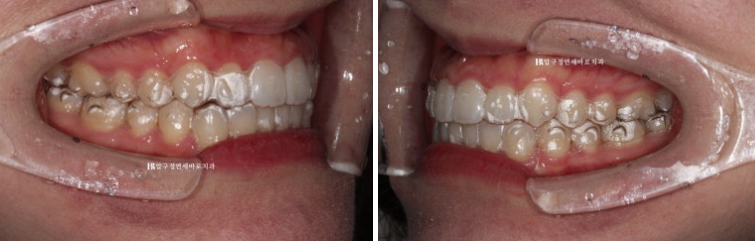

23.07

파란 화살표는 송곳니끼리 거꾸로 물리는 반대교합도 보입니다.

앞니가 삐뚤하고 아래 악궁 모양이 둥글지 않고 네모진 형태입니다.

어금니 교합은 좋았기에 인비절라인 라이트로 교정치료 권유드렸습니다.

23.11

4달간 인비절라인라이트에서 가능한 14개의 장치를 모두 낀 후 모습입니다.

7일에 하나씩 교체할 경우 14개의 장치를 다 끼면 약 4달의 시간이 흐릅니다.

배열이 잡혀 가지런해졌으나

송곳니 반대교합이 아직 남아있고 중심선이 개선이 되긴 했으나 완벽하게 맞지 않습니다.